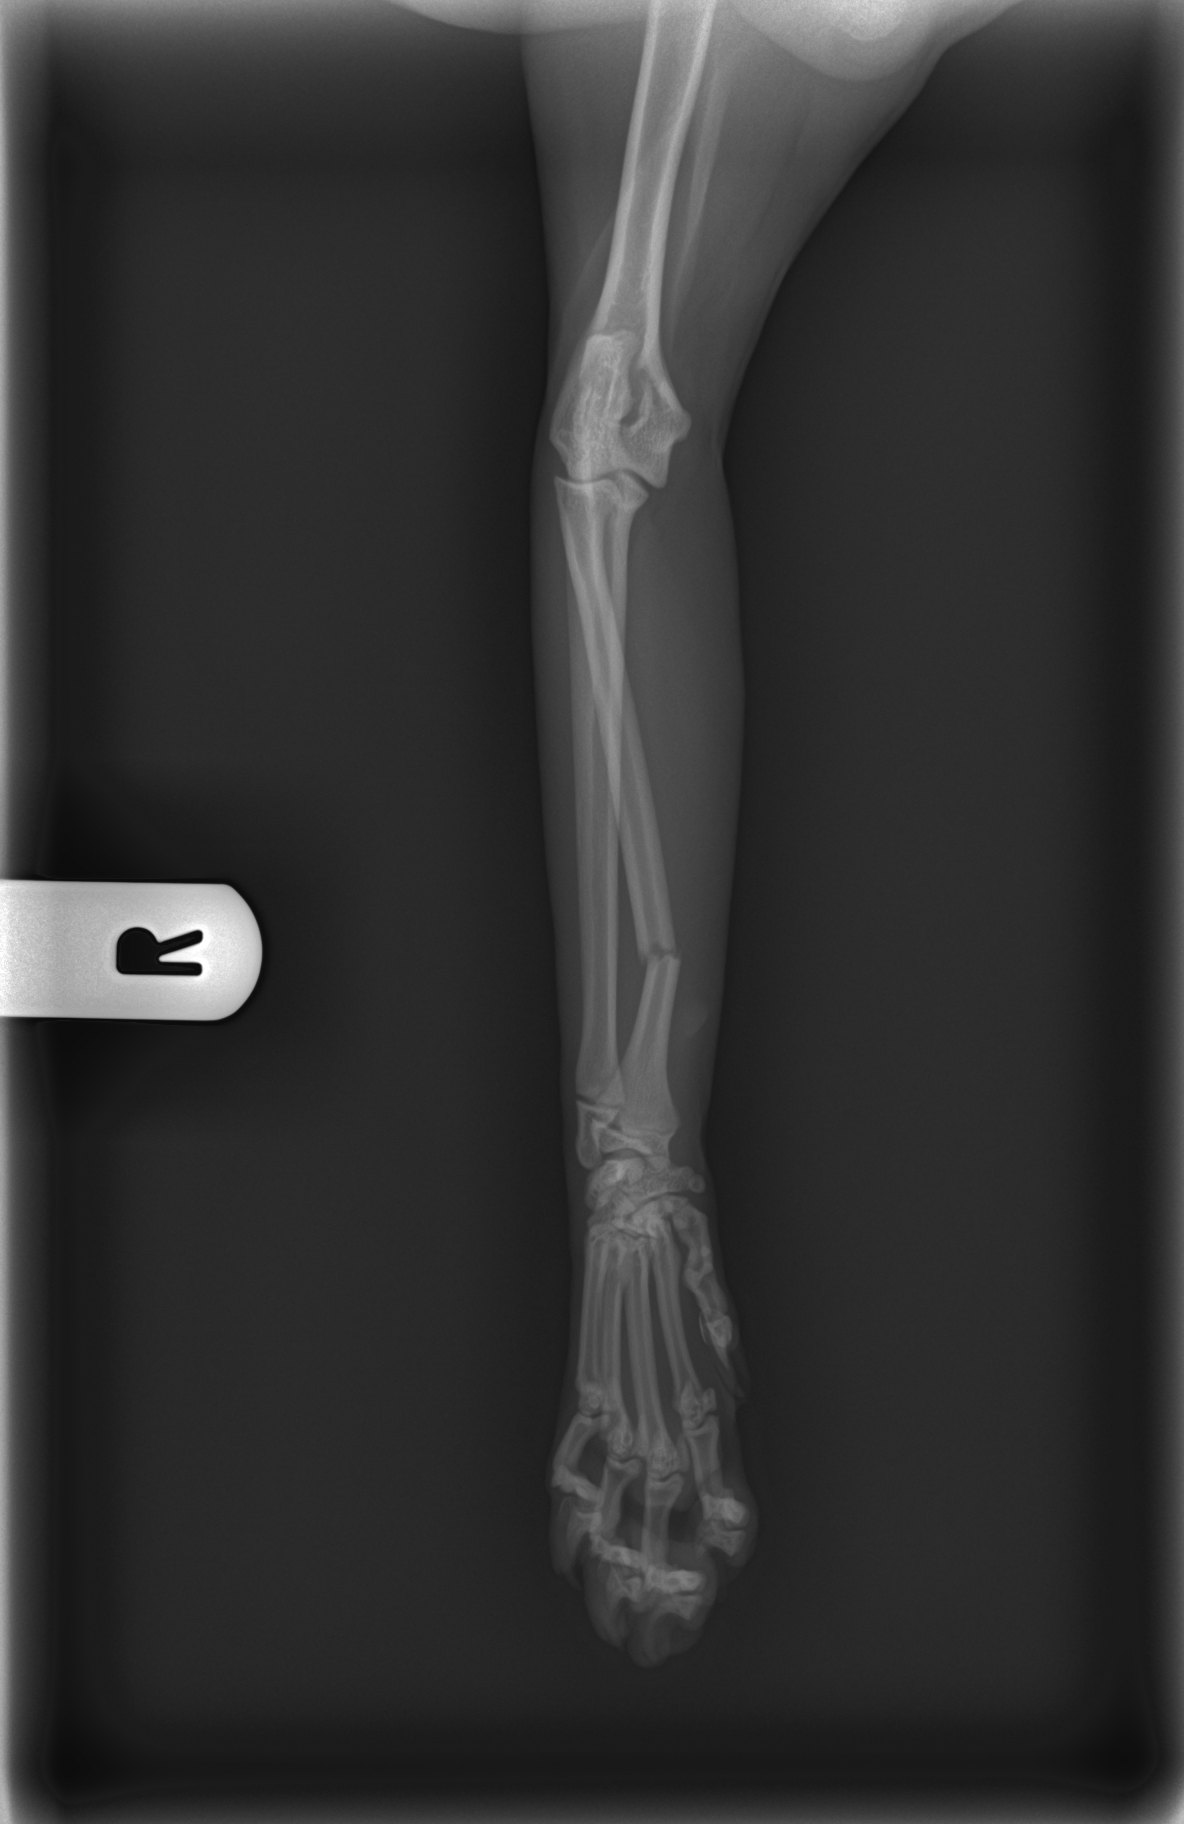

Levamo-lo de imediato ao veterinário, onde foi feita uma ecografia abdominal que, felizmente, não mostrou alterações internas. No entanto, o raio-x revelou fraturas, no rádio da pata dianteira direita e no metacarpo da pata dianteira esquerda.